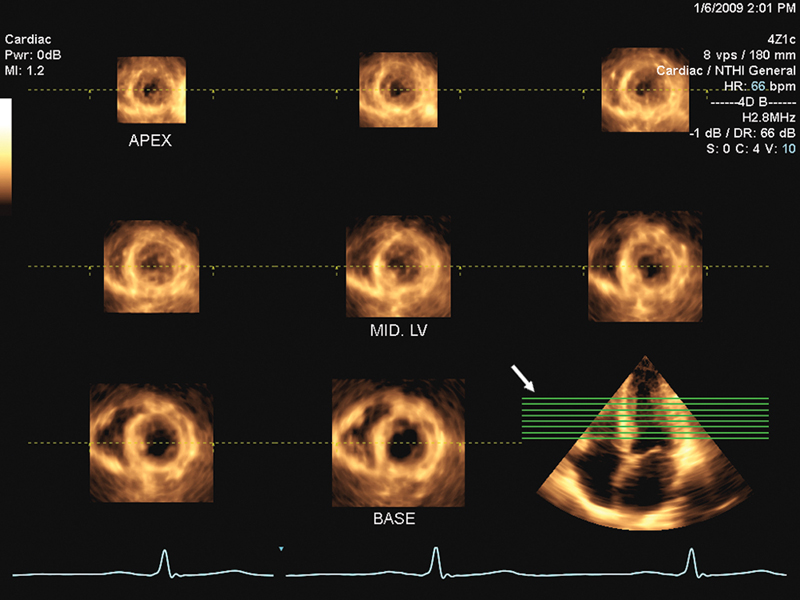

فحوصات تشخيصية لبعض امراض القلب والشرايين التاجية